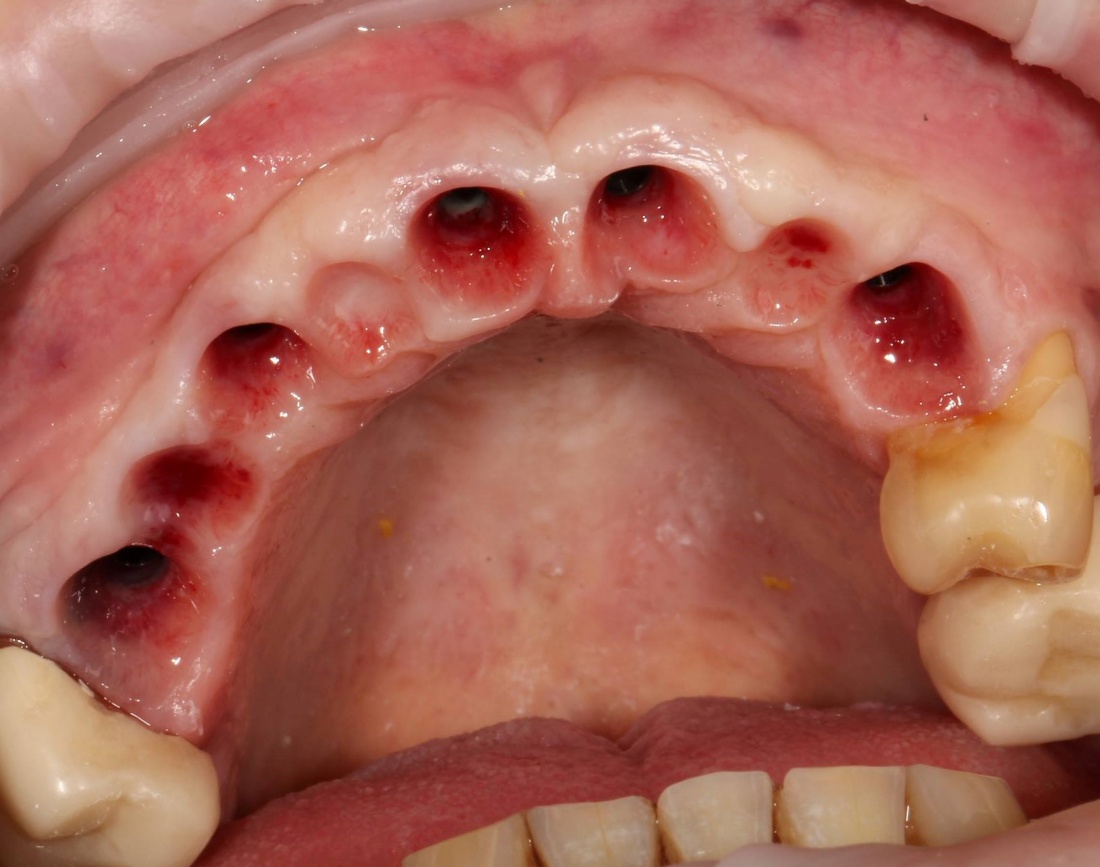

Итак, Зинаида на приеме.

Вот клиническая картина через 4 месяца после ранее проведенной имплантации с остеопластикой:

Устанавливаем формирователи десневой манжеты. Сегодня я называю эту процедуру не менее важной, чем любой другой этап имплантологического лечения:

И швы. Просто швы. Никаких дополнительных процедур.

Если честно, то сейчас бы я использовал другой шовный материал и другой тип швов. Одно неизменно, — и я об этом много раз говорил, — самая широкая часть формирователя десны должна находиться на уровне десны. Так, чтобы эффективно отрабатывать т. н. «биологическую ширину».

Через неделю я снял швы, а мой коллега Андрей Карнеев (дело было еще в НИЦ) приступил к изготовлению протезов. На это ушло полторы недели: